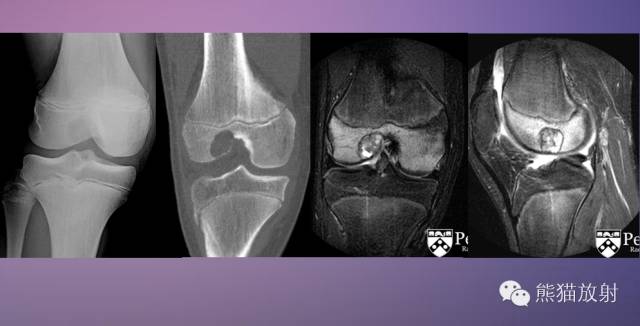

↓ 胫骨上端骨巨细胞瘤

IB型 ↓ 软骨母细胞瘤(男10岁)